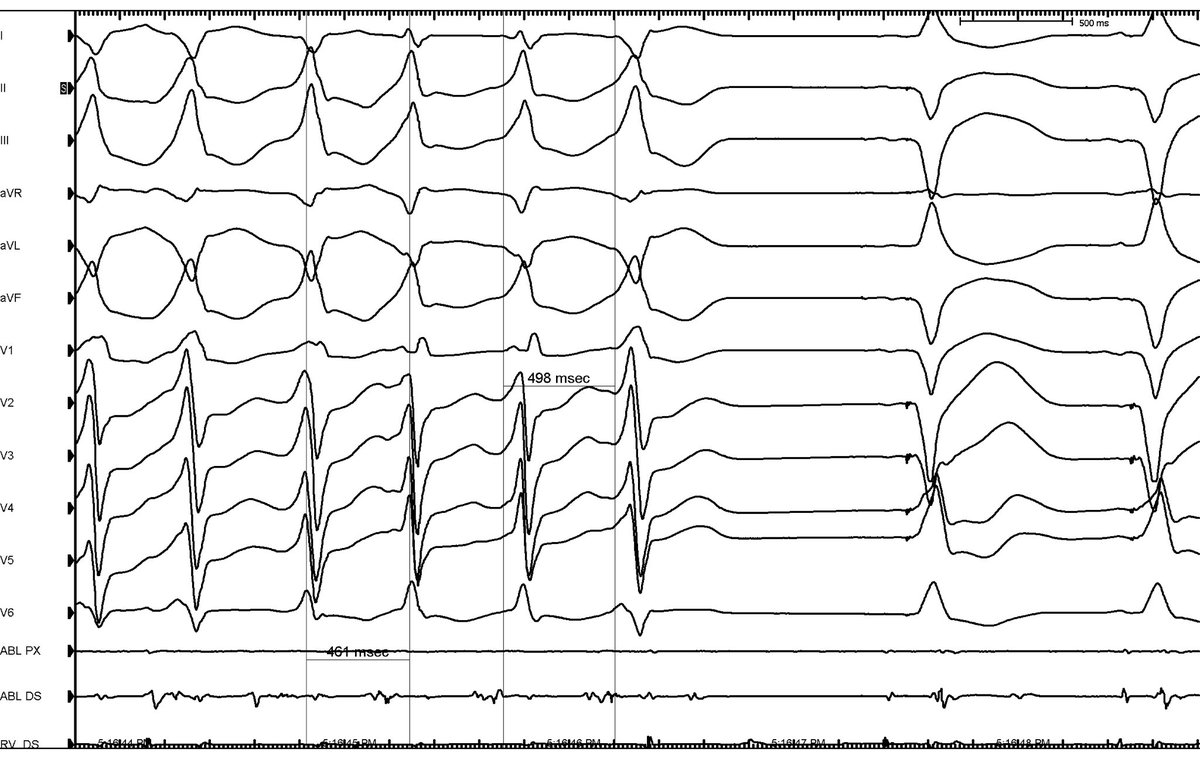

Amazing finale for super @MUSC_EP fellow @DanBLevinMD with novel work exploring intracardiac fiducial point for OT PVC localization. Thanks to @shivkumarmd @BradfieldMD for helpful improvements- @MUSCCardFellows @JACCJournals